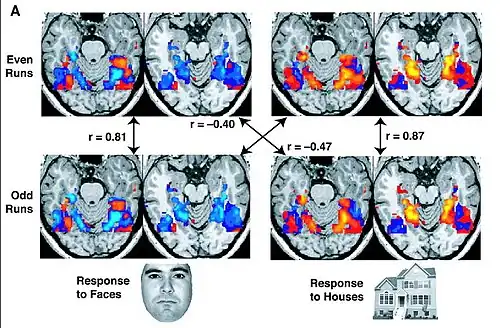

Functional connectivity is the connectivity between brain regions that share functional properties. More specifically, it can be defined as the temporal correlation between spatially remote neurophysiological events, expressed as deviation from statistical independence across these events in distributed neuronal groups and areas.[21] This applies to both resting state and task-state studies. While functional connectivity can refer to correlations across subjects, runs, blocks, trials, or individual time points, resting state functional connectivity focuses on connectivity assessed across individual BOLD time points during resting conditions.[22] Functional connectivity has also been evaluated using the perfusion time series sampled with arterial spin labeled perfusion fMRI.[23] Functional connectivity MRI (fcMRI), which can include resting state fMRI and task-based MRI, might someday help provide more definitive diagnoses for mental health disorders such as bipolar disorder and may also aid in understanding the development and progression of post-traumatic stress disorder as well as evaluate the effect of treatment.[24] Functional connectivity has been suggested to be an expression of the network behavior underlying high level cognitive function partially because unlike structural connectivity, functional connectivity often changes on the order of seconds as in the case of dynamic functional connectivity.